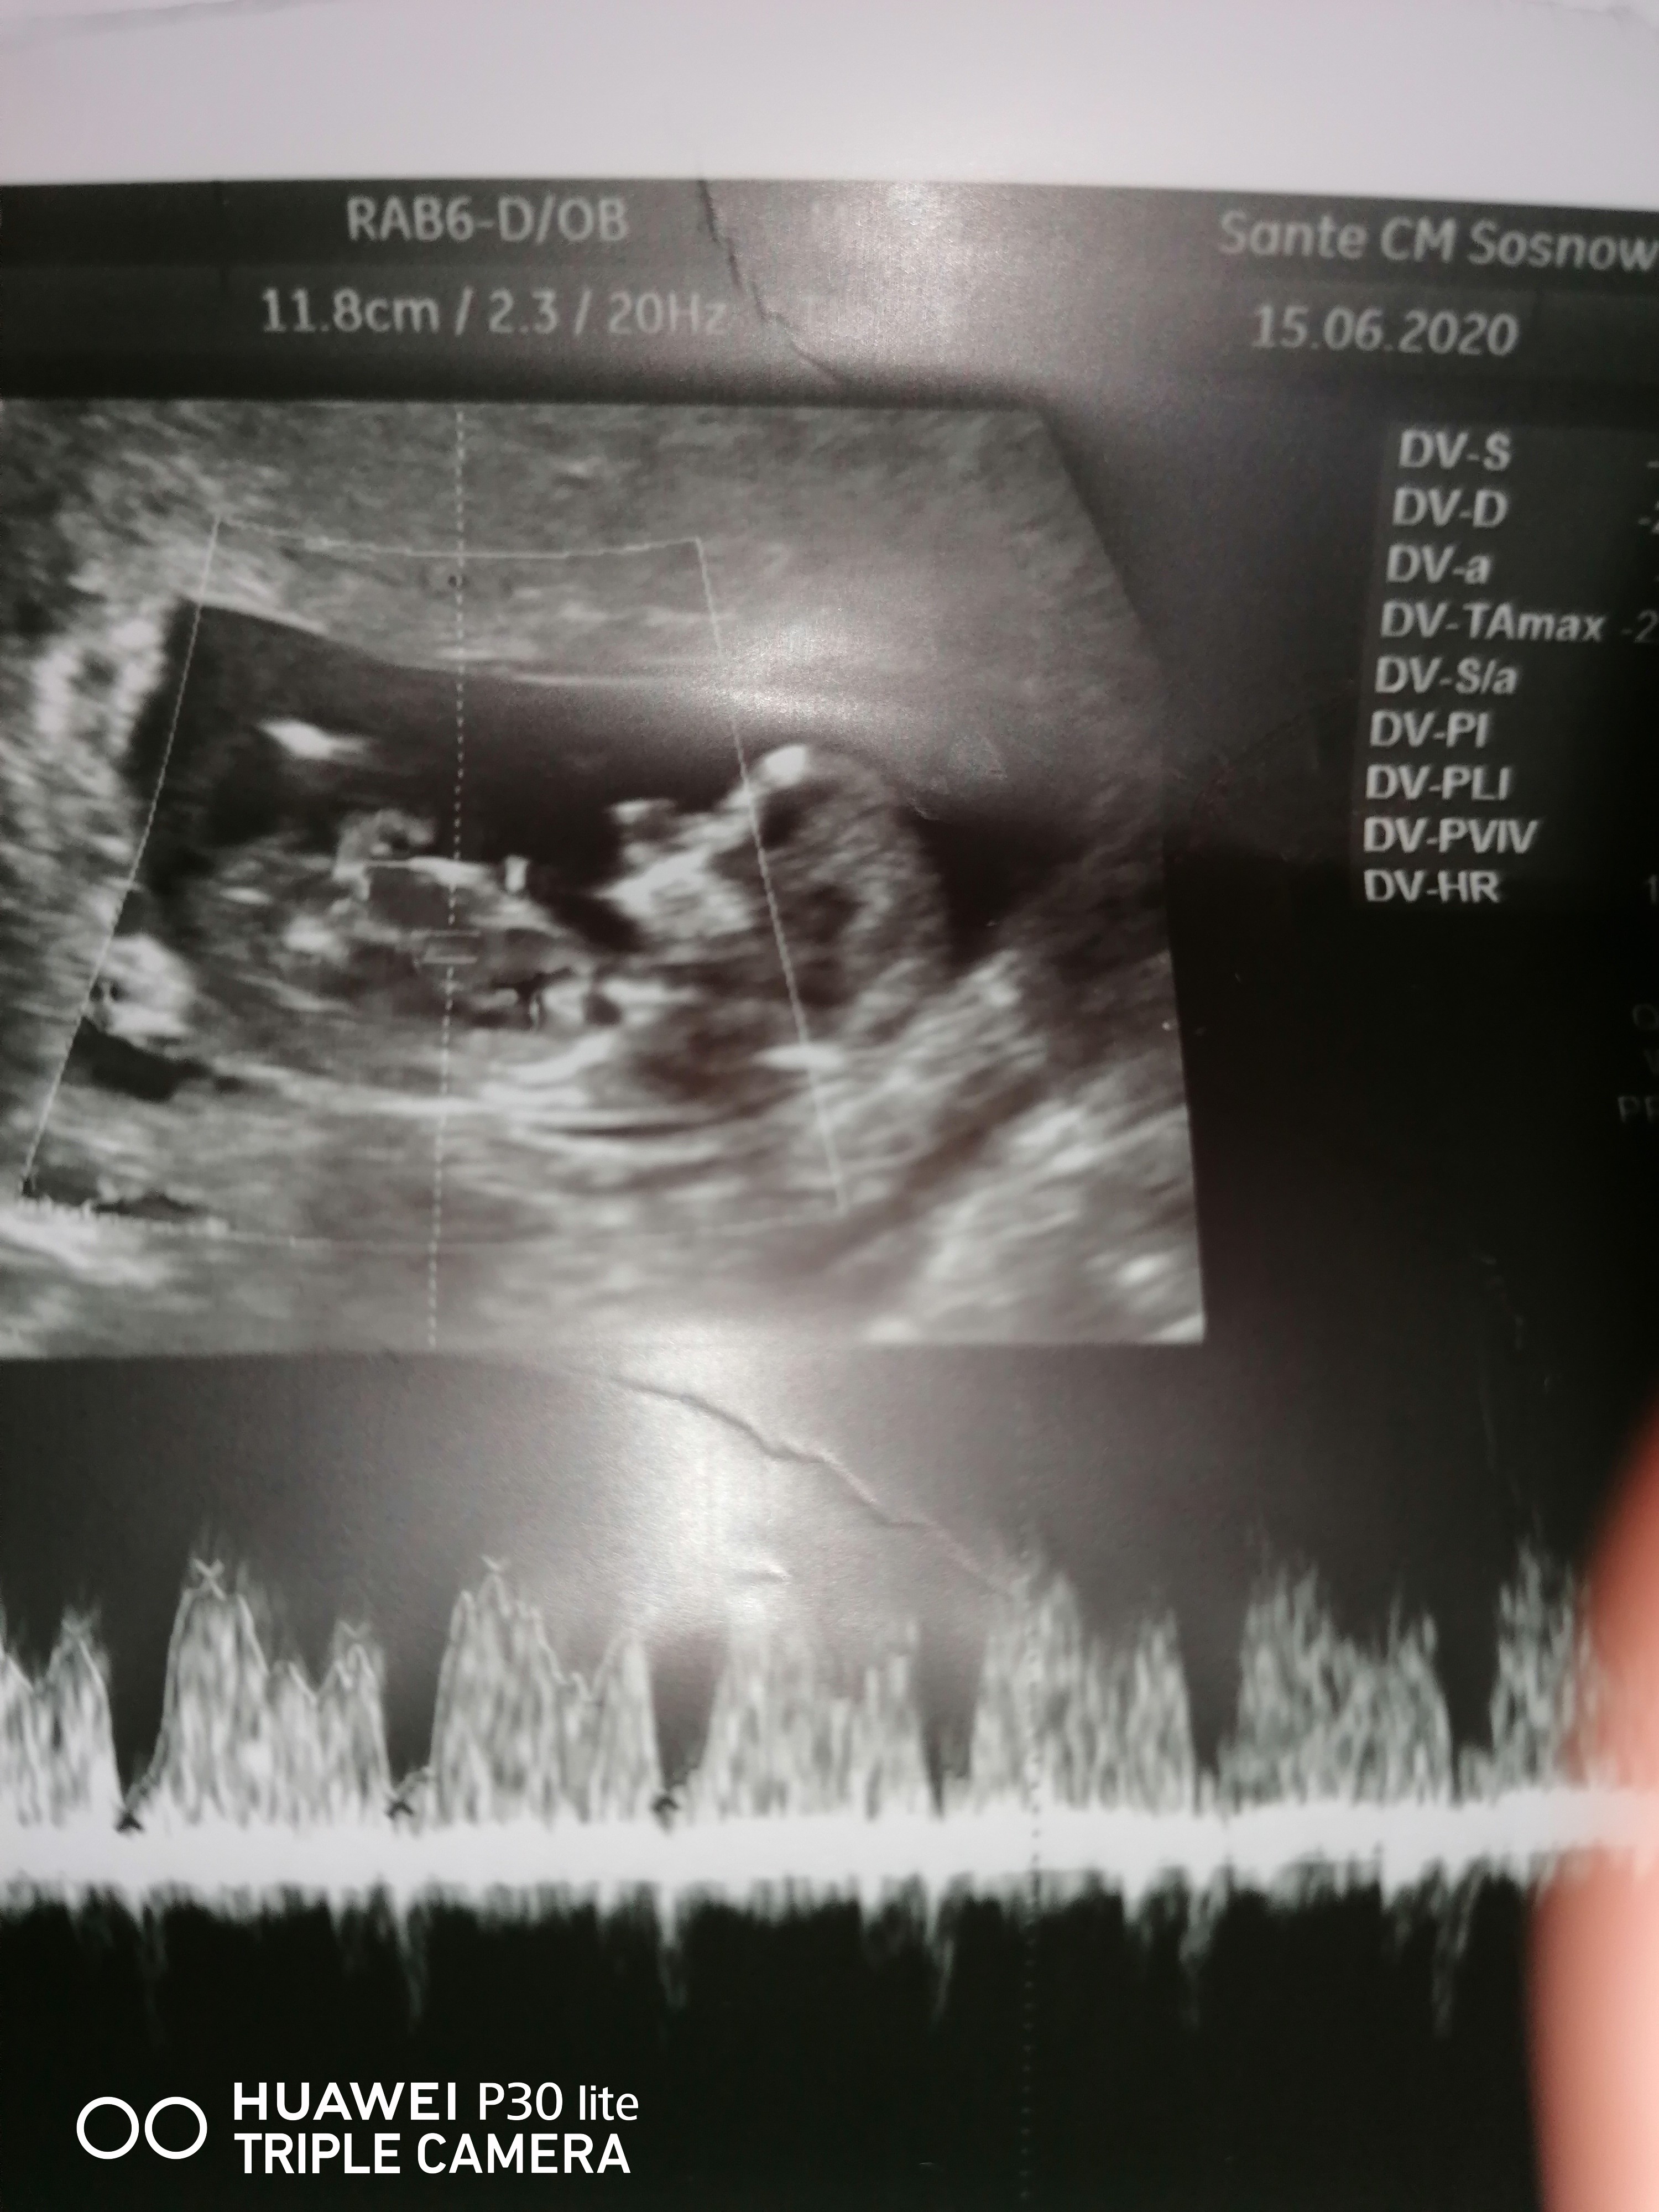

Hej Wam ja dzis prenatalne miałam😊😊 maleństwo ma sie super. Wszystko w normie. Na 75% Pani dr powoedziała, że widzi chłopca 🥰 ale nie nastawiam sie za bardzo na płec ale ważne ze zdrowe 🤩

• IMG_20200615_115022.jpg

IMG_20200615_115022.jpg

1,4 MB · Wyświetleń: 98